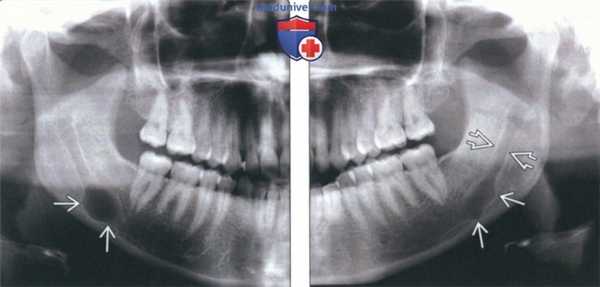

(Слева) На панорамной рентгенограмме у девушки 24 лет определяется однокамерный расширенный участок правого нижнечелюстного канала с четкими контурами. Рентгеновская картина типична для шванномы. Симптоматика у пациентки отсутствует, расширение канала было обнаружено случайно.

(Справа) На панорамной рентгенограмме у этой же пациентки определяется не столь равномерное вздутие нижнечелюстного канала слева. Обратите внимание на некоторое расширение канала сзади от пораженного участка, как на противоположной стороне.